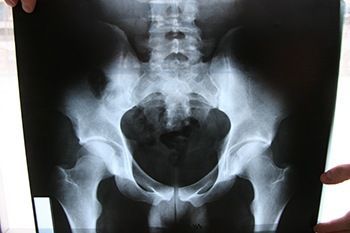

Рентген крестца

Кость крестца имеет треугольную форму и состоит из пяти позвонков, располагаясь между костями таза и формируя заднюю часть его полости. Эта часть позвоночного столба выполняет важные функции в организме человека, включая обеспечение вертикального положения тела и правильное распределение нагрузок на анатомические структуры тазовой области. Рентген крестца — неотъемлемая составляющая диагностики его заболеваний.